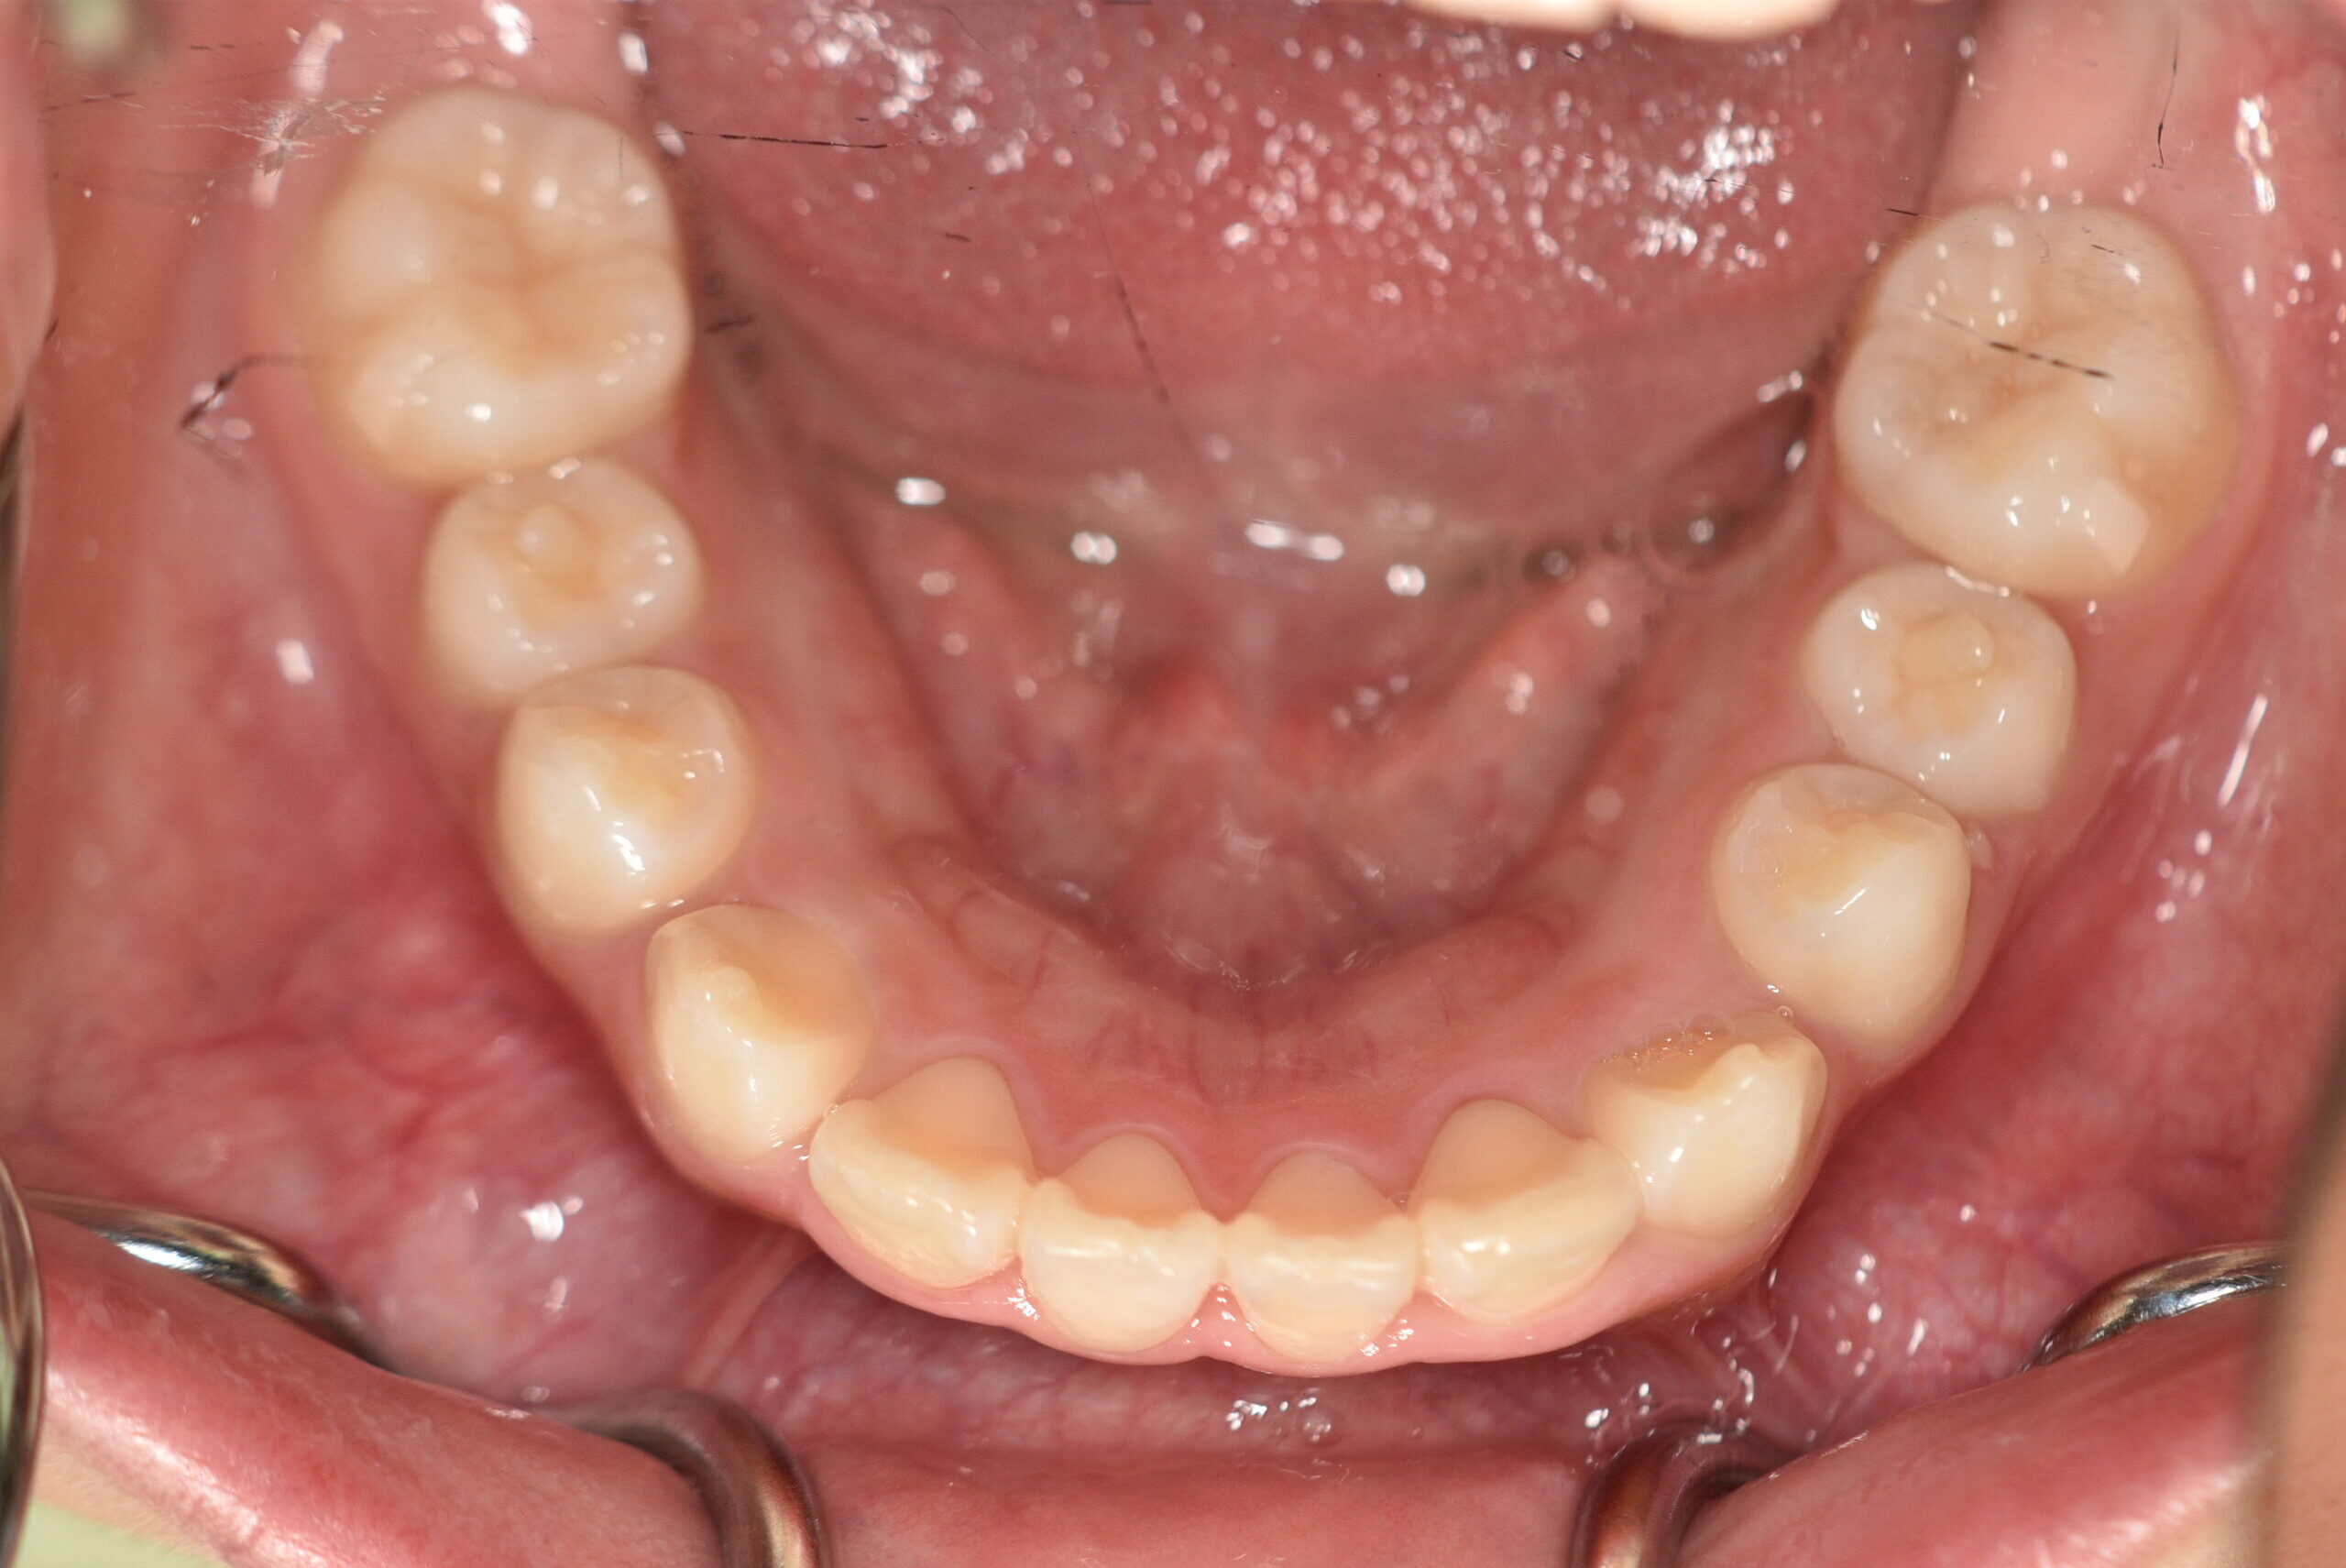

| 治療内容の詳細 | 初診時7歳の女児で、歯のがたつきを気にされ来院されました。 検査の結果、前歯部叢生を伴うアングルⅡ級不正咬合と診断しました。 治療としてはマウスピース矯正(インビザラインファースト)で配列を行い、上下顎の側方拡大と萌出スペースを確保しました。 治療期間は、1年でした。 今後、側方歯生え変わりまで経過観察を行います。 |